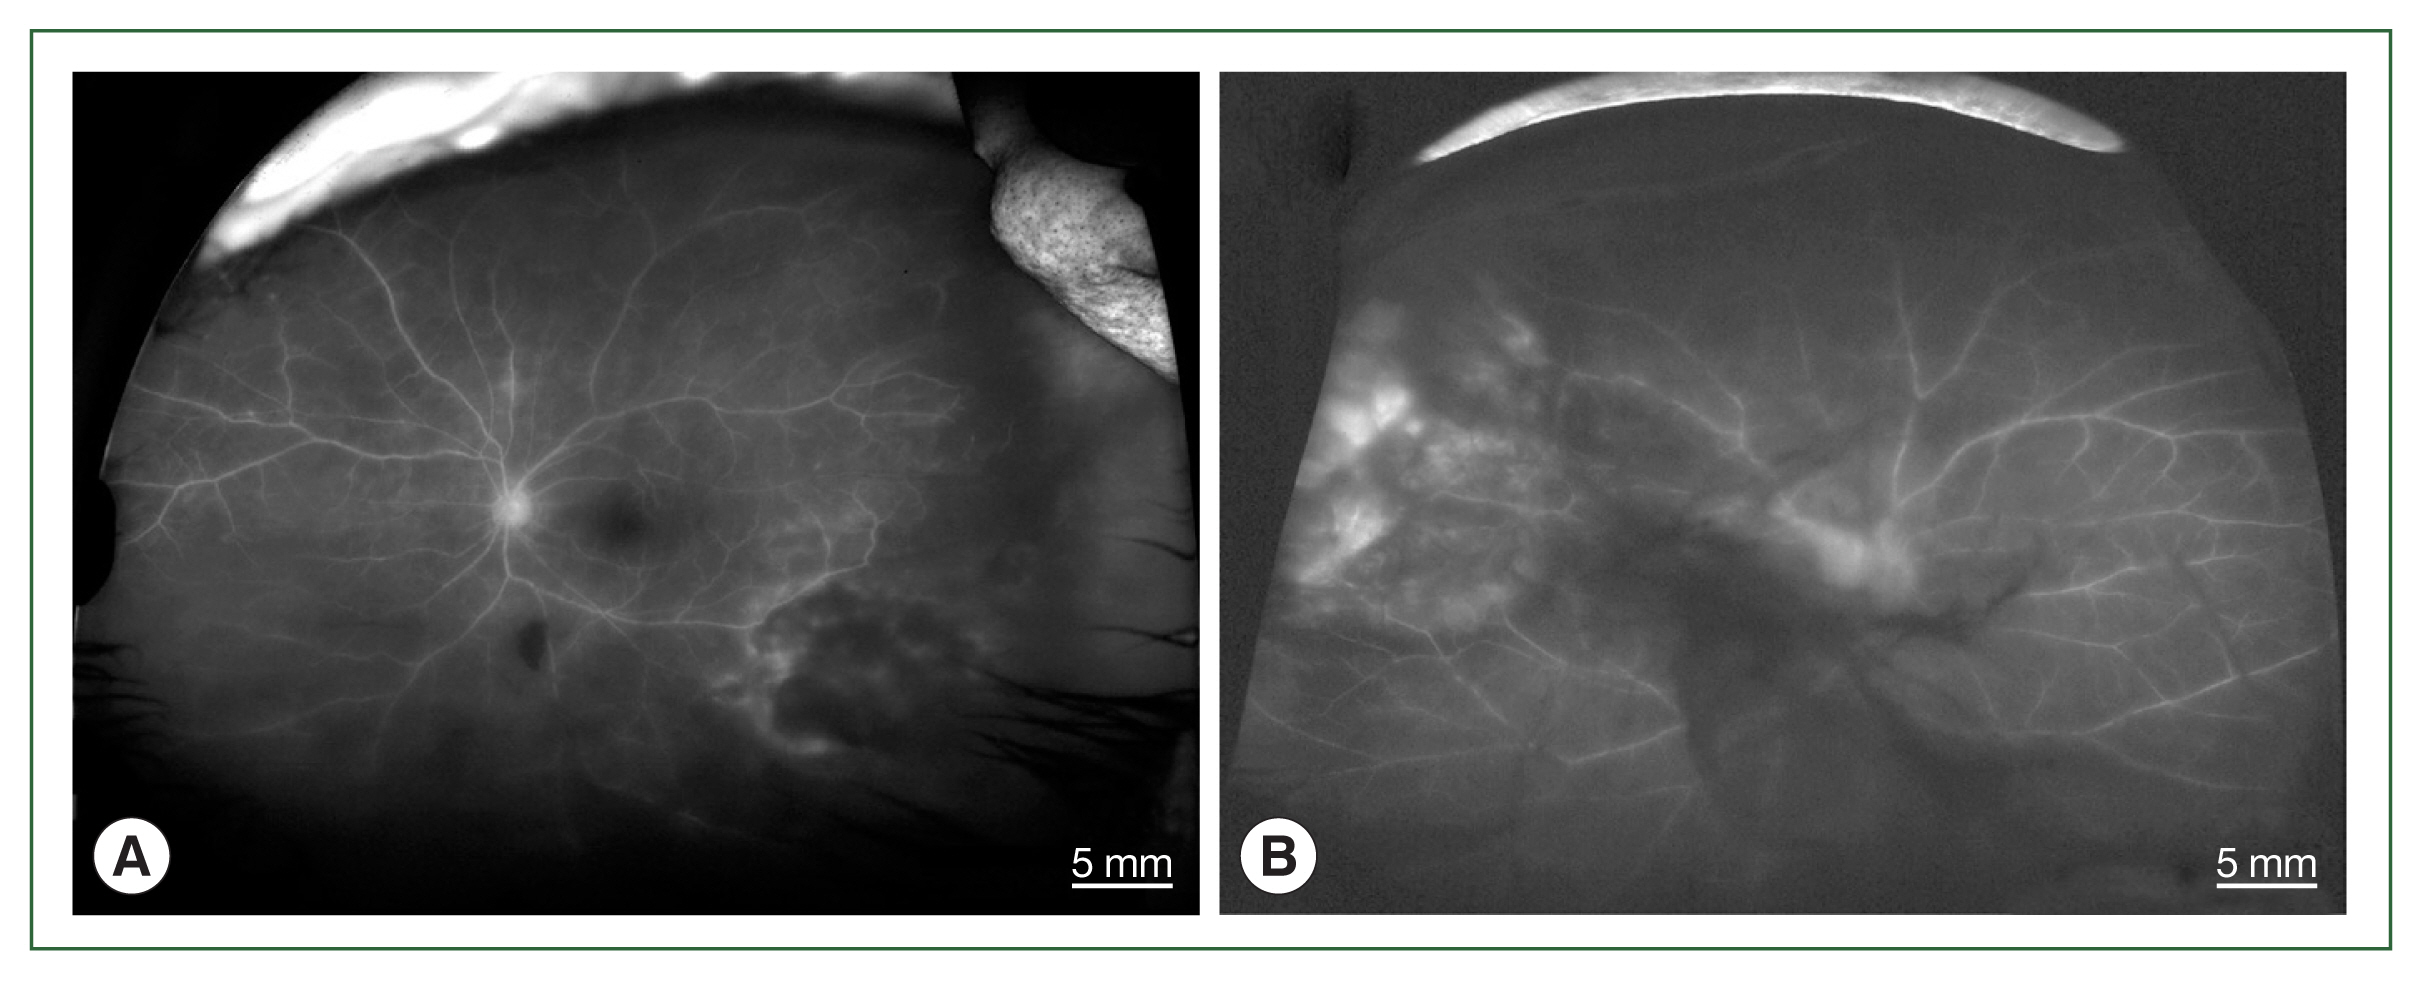

Fig. 2

Fundus fluorescein angiographs of papillitis and vasculitis in an ocular toxoplasmosis patient; (A) left eye of case 1, (B) right eye of case 4.

The 4 patients presented persistent unilateral visual disturbance 2–3 months before assessment. The ocular examination revealed that all study patients also exhibited unilateral panuveitis. Two patients (cases 1 and 2) did not show signs of chorioretinal scars, while the other 2 patients (cases 3 and 4) had preexisting scars on the retina and choroid. All of them showed an initial decimal visual acuity between 0.1 and 0.5. The ophthalmic analysis also revealed active retinochoroiditis in the 4 patients (Fig. 1) and papillitis and periphlebitis in cases 1 and 4, which were more evident by fundus fluorescein angiography (Fig. 2). All study patients also exhibited vitritis and anterior uveitis. Three patients (cases 1, 3, and 4) who underwent vitrectomy for diagnostic and therapeutic reasons had negative cytology for lymphoma cells. The remaining patient (case 3) had re-vitrectomy combined with scleral encircling for total retinal detachments developed later (Fig. 3). Only 1 patient (case 1), who was previously diagnosed with acute retinal necrosis (ARN) in a local ophthalmology clinic, received a systemic steroid treatment (60 mg per day) for posterior uveitis before visiting the Eye Center at the Seoul St. Mary Hospital, Catholic University. None had received any medication (including antibiotics) before the examination.